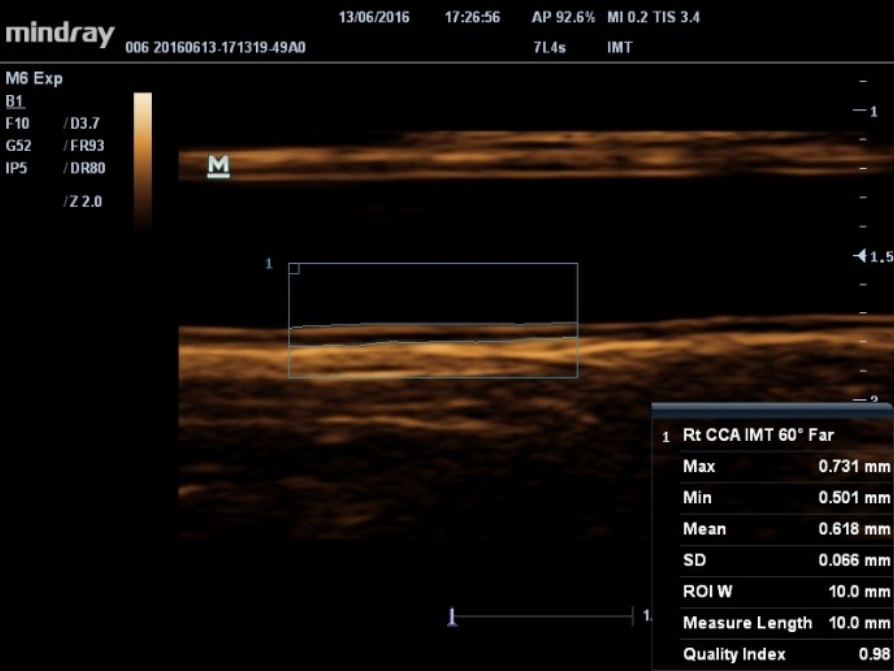

Auto measurement of anterior and posterior wall thickness providing accurate carotid status.